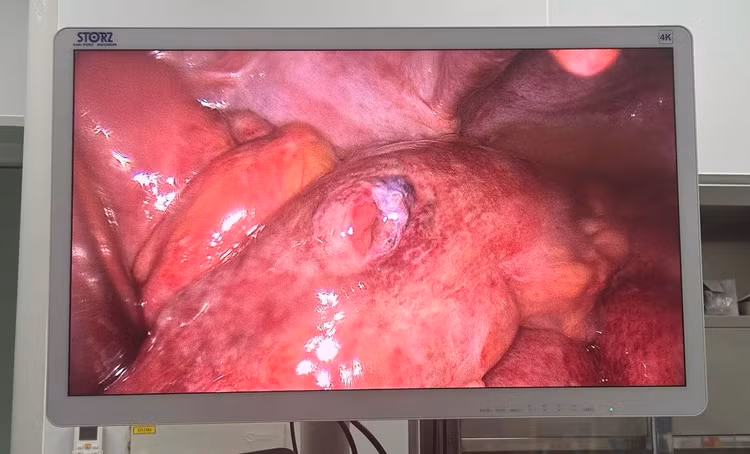

![]() |

| Hình ảnh thủng ruột trên nội soi - Ảnh BVCC |

Ngay lập tức, BS Hoàng Minh Hùng trực cấp cứu khoa Ngoại Tổng hợp đã chỉ định phẫu thuật nội soi khẩn cấp. Trong quá trình mổ, kíp phẫu thuật phát hiện ổ bụng nhiễm bẩn nặng, có một lỗ thủng ruột non và một lỗ thủng đại tràng Sigma vùng chậu hông. Các bác sĩ đã tiến hành rửa sạch ổ bụng, khâu phục hồi ruột non và mở hậu môn nhân tạo tại vị trí thủng đại tràng.